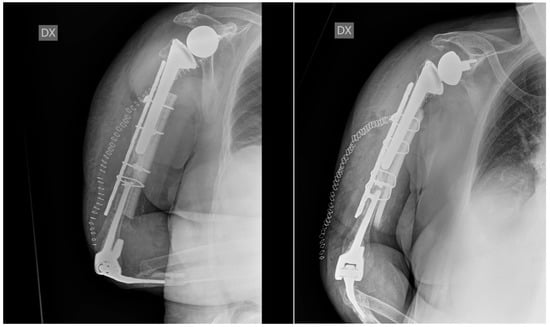

The patient was set up in a beach chair position. An extended deltopectoral approach was chosen; a careful, blunt dissection of the surrounding soft tissues was then performed, proceeding deeply into the muscular part of the biceps brachii and brachialis, both of which showed a high grade of contusion. The radial nerve was individualised at the spiral groove and laterally protected throughout the surgery. The ulnar nerve was also visualised and isolated and protected throughout the procedure. At the level of the fracture, the cement leak was noted and removed, and the tip of the shoulder stem was tested and appeared to be stable. Due to very poor bone quality, a synthetic bone graft associated with growth fracture in a mesh form and a strip form (Bone Graft I-Factor, Cerapedics) was inserted at the fracture site, and the supportive medial bone graft from the equinus femur was also inserted as a mechanical strut (Bioplant-Activia, 150 × 20 × 6 mm equine bone graft). The fracture was reduced and stabilised under fluoroscopy with a 4.5/5 mm eight-hole reconstruction plate, further stabilised by four cerclages (DePuy-Synthes cerclage system) with a tension of 45 Nm. The stability was tested, and the fixation was deemed to be stable. Accurate haemostasis was provided throughout the surgical procedure. Wound closure was performed in layers. A Gilchrist bandage was applied. One blood transfusion was administrated on the second postoperative day, and no other perioperative complications occurred during the hospitalisation. A routine wound check was carried out till clip removals. The post-op laboratory results were in the range after the second post-op day. The postoperative X-rays on the first postoperative day showed good alignment and stability of the construct (Figure 3).

Figure 3.

Postoperative X-ray at 1 day. The X-rays show good reduction and alignment of the fracture, good fixation and strut position, and stability of the previously implanted shoulder and elbow prostheses.